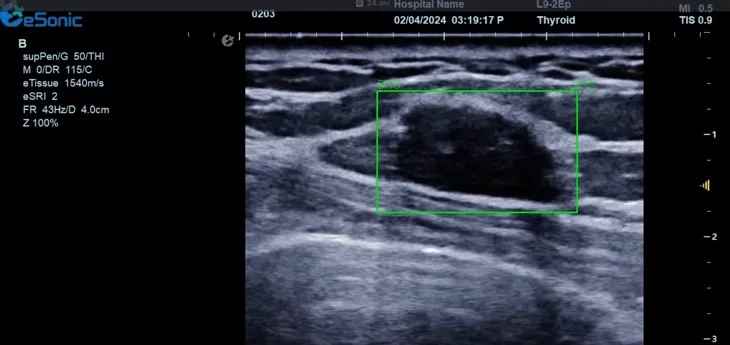

银河官网医疗(ESI)表示,其最新的人工智能功能可以帮助到医疗机构的工作效率,功能包括,实时、动态、快速自动识别病灶,良恶性病灶概率预测,甲状腺结节和乳腺的二维灰阶动态自动实时检测需求,提供多个结节动态检测轮廓框。实时获取多幅具备临床特征(大小、属性等)的结节切面,同时提供当前切面所示结节的结节大小、属性特征、TI-RADS 分级。

对于甲状腺结节相关的自动检测功能,甲状腺结节病灶检出率≥95%,良恶性分类灵敏度≥90%、良恶性分类特异度≥85%。